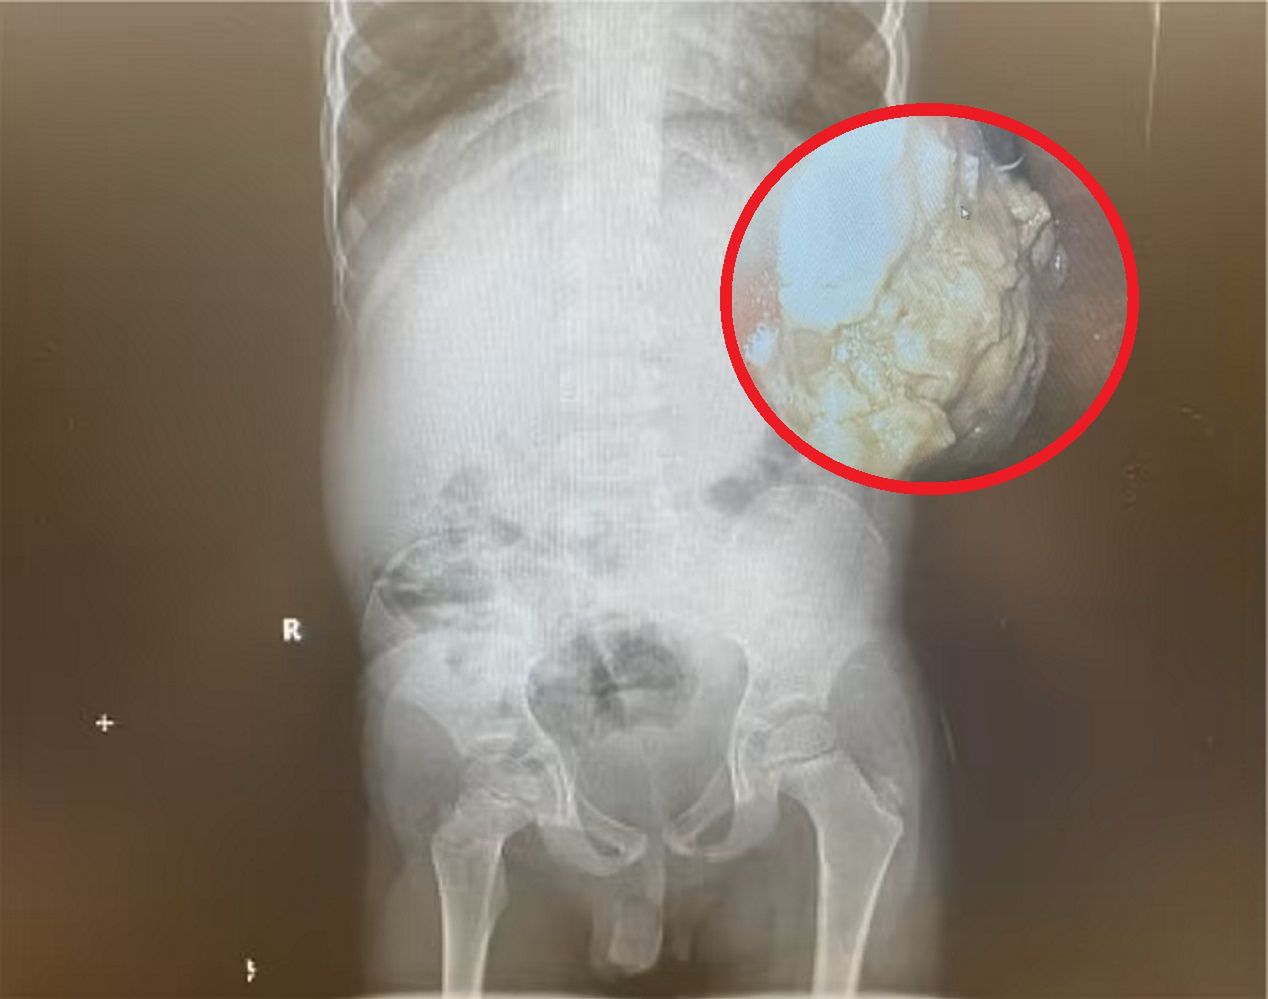

We wrześniu 2022 roku, Zoe Plastrias, będąca wtedy w ósmej miesiącu ciąży, zaczęła zauważać niepokojące objawy. 23-letnia kobieta doświadczała dyskomfortu związanego z oddychaniem, szybciej męczyła się i nawiedzały ją uporczywe bóle głowy. Początkowo przypisywała te symptomy schyłkowym etapom ciąży, ale kiedy pewnego dnia ledwo mogła łapać tchu, postanowiła skontaktować się z pogotowiem.

Konsultant z pogotowia zalecił jej natychmiastowe zgłoszenie się do najbliższego szpitala. Tam wykonano dla niej szereg badań, w tym badanie krwi i prześwietlenie klatki piersiowej. Diagnoza, która zszokowała młodą kobietę brzmiała "drobna wada serca". Zoe została wypisana do domu z zaleceniem kontynuowania monitoringu.

Rankiem następnego dnia, Zoe zauważyła na swoim telefonie 12 nieodebranych połączeń, a także kilka teraźniejszych wiadomości tekstowych od personelu szpitala: wzywającej ją do jak najszybszego stawiennictwa na oddziale kardiologicznym. Młoda kobieta natychmiast udała się do szpitala.

- Pielęgniarka zapytała mnie, ile chcę wiedzieć. Odpowiedziałam natychmiast, że muszę wiedzieć wszystko, bo niedługo zostanę mamą. To właśnie wtedy dowiedziałam się, że w mojej klatce piersiowej zlokalizowany jest guz wielkości grejpfruta, a lekarze podejrzewają nowotwór - opowiada.

Nowotwór wielkości grejpfruta

Zoe i Joe, jej życiowy partner, stanęli w obliczu ogromnego dramatu. Zoe natychmiast została skierowana na dokładne badania medyczne. Medycy odkryli, że blisko 12-centrymetrowy zlokalizowany był w bezpośrednim sąsiedztwie serca. Wykonana biopsja potwierdziła, że jest to chłoniak nieziarniczy w drugim stadium.